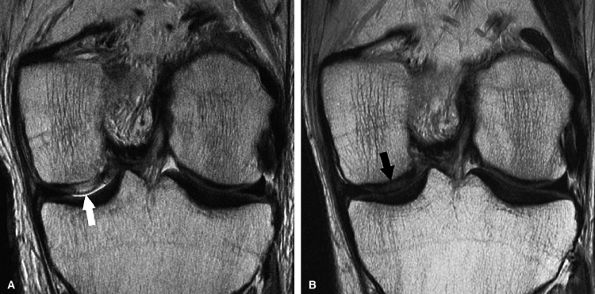

FIGURE 7.27 ● (A) Coronal fast spin-echo MR image of the knee in a 13-year-old girl obtained 3 months following autologous osteochondral transfer for osteochondritis dissecans of the medial femoral condyle. Despite the relatively thin cartilage over the proud osseous component of the osteochondral plug, there is good restoration of the radius of curvature of the articular surface. Note that the donor site in the lateral femoral condyle close to the notch is filled with autologous bone, covered by reparative material that is hyperintense to native cartilage. (B) Corresponding quantitative T2 relaxation time map coded to capture T2 values ranging from 5 to 100 msec demonstrates prolongation of T2 relaxation times at the margins of the osteochondral lesion (arrows). There is prolongation of T2 values at the margins of the plugs (arrows) and over the donor site (arrowhead), reflecting reparative fibrocartilage and a less organized matrix. Green and blue reflect longer T2 values, yellow intermediate, and orange the shorter values. (Reprinted by permission of SAGE Publications, Inc., from Am J Sports Med, in press.)

|